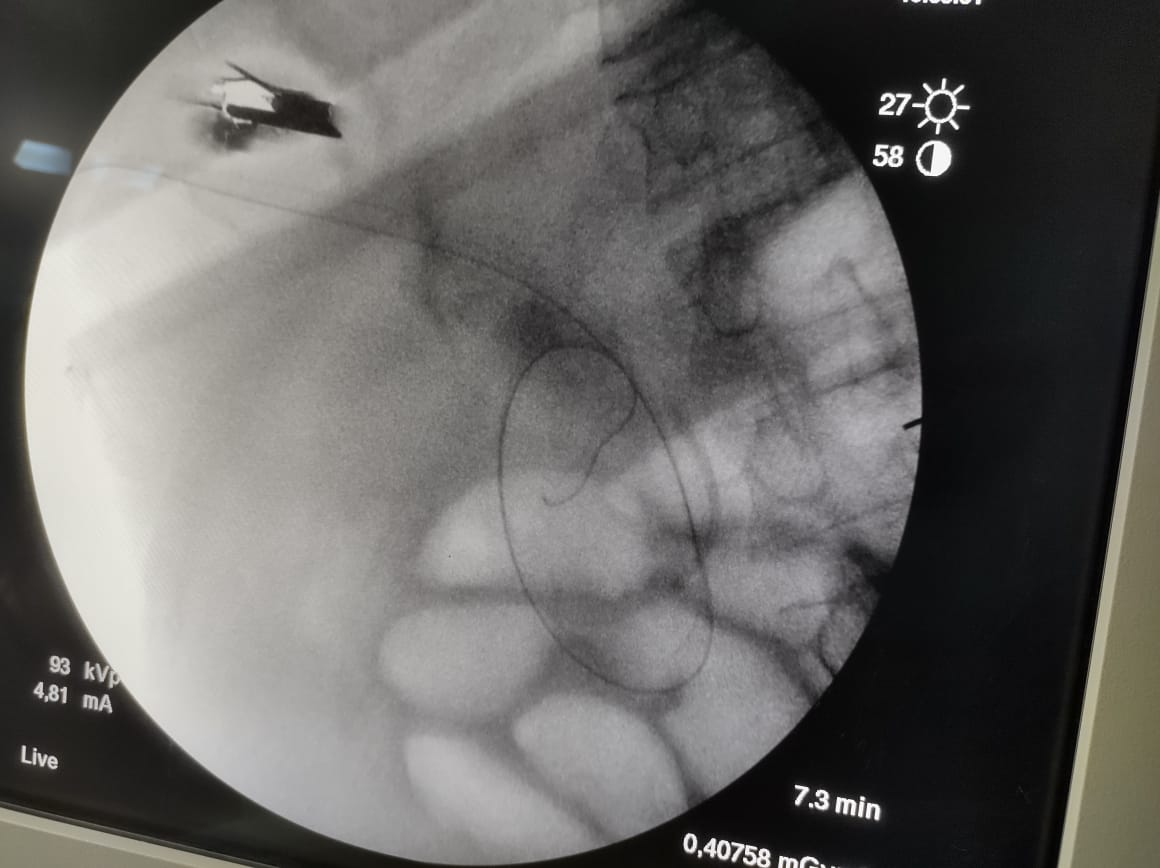

قال بيان الهيئة، إنه تم إجراء عملية راندڤو، ناجحة لمسن يعاني من صفراء انسدادية، وخلال العملية يتم استخدام المنظار والأشعة التداخلية معًا، وذلك لأول مرة تحت مظلة التأمين الصحي الشامل الجديدة، مشيرًا إلى أنه بمراجعة التاريخ المرضي للمنتفع، تبين أنه قام بإجراء عملية قلب مفتوح منذ 7 أشهر، مع وجود فشل في وظائف القلب وارتجاع في الصمام المترالي.

تابع البيان: تم عمل محاولتين لعمل منظار قنوات مرارية للمنتفع المشار إليه، وكانتا غير ناجحتين، وعليه تم تحضير المريض لإجراء عملية راندڤو، والتي تتم بمُشاركة استشاري المناظير مع استشاري الأشعة التداخلية، وذلك لإزالة سبب انسداد القنوات الصفراوية مع تركيب دعامة له، وذلك تحت مظلة التأمين الصحي الشامل، دون تحميل المريض أكثر من 300 جنيه فقط نسبة مساهمة.

نوه الدكتور مصطفى شعبان، مدير فرع الهيئة ببورسعيد، بأن مزايا عمليات المناظير عديدة لا تتوافر في الجراحات المفتوحة مثل سرعة التعافي وقِصر المكوث في المستشفى، والعودة السريعة لممارسة الحياة الطبيعية، لافتًا إلى أن تقنية راندڤو، هي تقنية تجرى لأول مرة على أرض بورسعيد، وأطلق عليها هذا الاسم، حيث يتلاقى المنظار والأشعة التداخلية داخل جسم المريض، بالمنطقة المصابة خلال العملية، مؤكدًا نجاح العملية وتماثل المريض للشفاء.